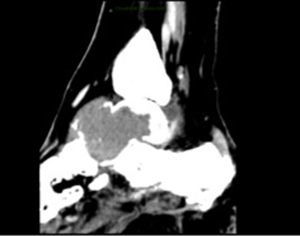

Caso clínicoPaciente mujer de 57 años de edad, que inicia cuadro clínico con sangrado transvaginal y dolor pélvico, por lo cual acude a valoración, se realizan estudios de extensión, entre ellos ultrasonido y toma biopsia endometrial, con reporte de AE y, por lo tanto, se le realiza histerectomía, linfadenectomía pélvica bilateral y paraaórtica con reporte histopatológico de adenocarcinoma endometrial de tipo endometrioide moderadamente diferenciado (G2), que infiltra a 0.1cm de la superficie serosa del útero, con extensión a ambos parametrios, con permeación linfovascular presente, sin evidencia de lesión en márgenes quirúrgicos, adenopatías negativas (EC II FIGO), por lo que recibe tratamiento con radioterapia externa 50.4Gy y braquiterapia intracavitaria. Durante su seguimiento, a 6 meses de terminado el tratamiento, refiere dolor intenso y edema en tobillo izquierdo, así como incapacidad para la deambulación. En las radiografías solicitadas observamos disminución en la densidad ósea de los huesos del tarso, y alteración en la morfología del hueso astrágalo (fig. 1). La tomografía axial computarizada de dicha región muestra lesión lítica expansiva de predominio en astrágalo con extensión a partes blandas y huesos del tarso (fig. 2), PET-CT con 18F-fluordesoxiglucosa (FDG) con actividad tumoral a nivel de hueso astrágalo izquierdo con lesión lítica expansiva y afección de tejido blandos adyacentes (fig. 3). Por tal motivo se le realiza biopsia de astrágalo con reporte histopatológico de AE moderadamente diferenciado metastásico (fig. 4). Se inicia tratamiento con radioterapia 30Gy en 10 fracciones, se difiere el apoyo y quimioterapia paliativa con paclitaxel y carboplatino en 6 ciclos, así como aplicación mensual de ácido zoledrónico, hasta completar 6 dosis. Actualmente, a 12 meses de detectada la enfermedad en el astrágalo izquierdo, la paciente presenta buena evolución, sin progresión de la enfermedad y tolerando la deambulación sin dolor (figs. 5 y 6).